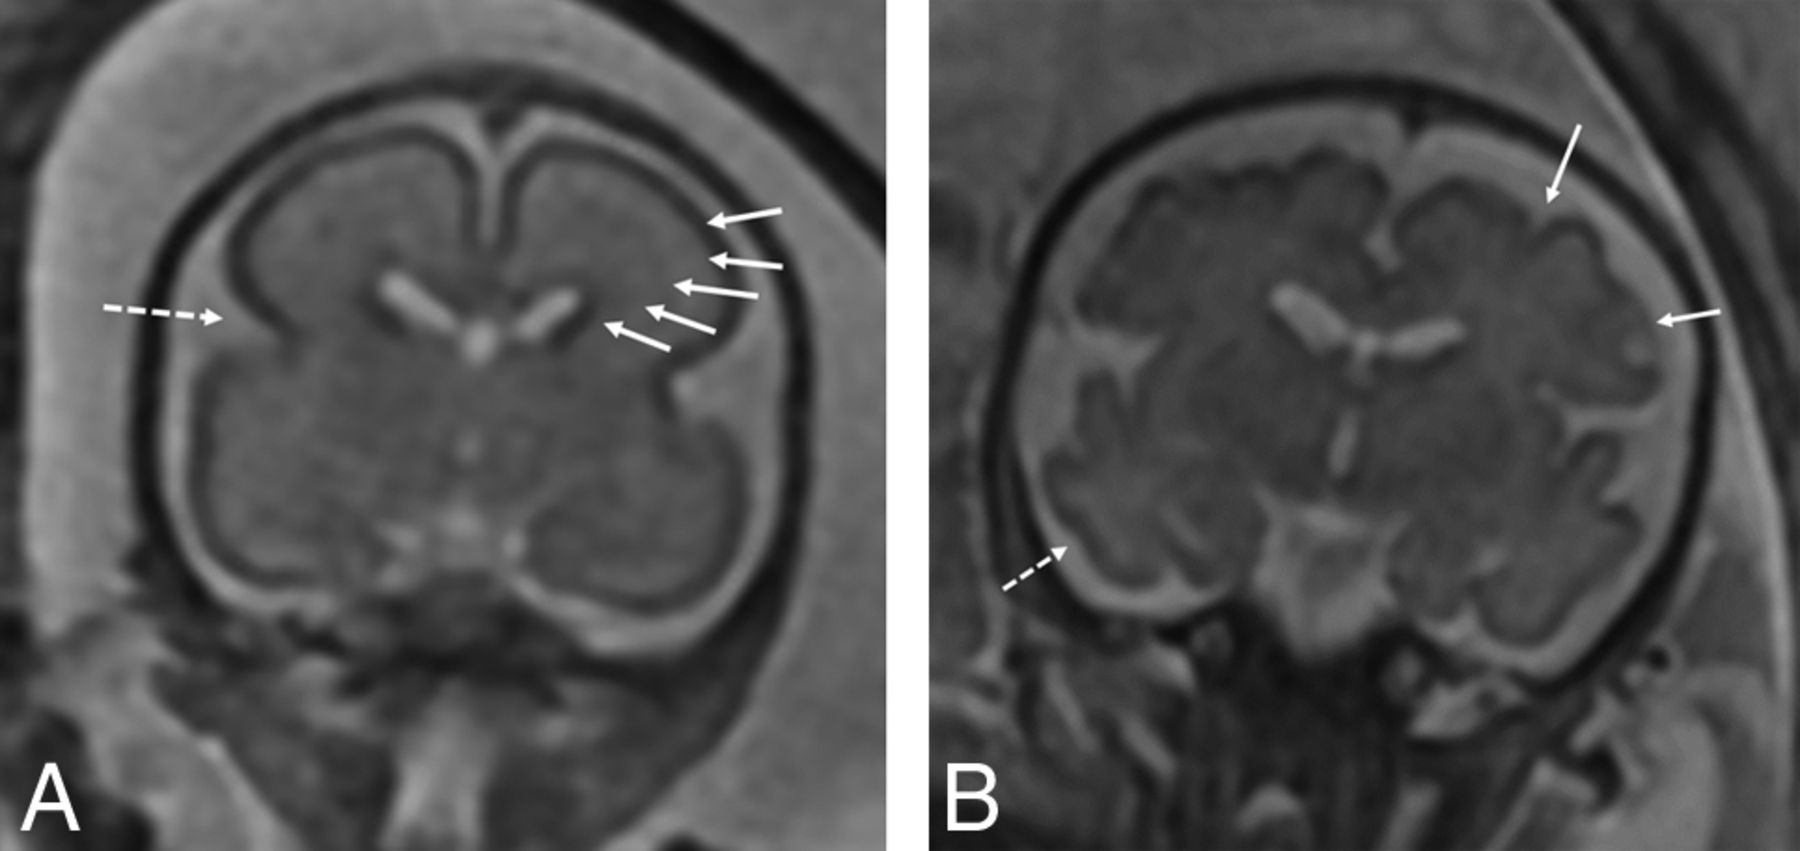

On fetal MR imaging, enlarged extra-axial spaces were the most common brain finding, seen in 22/36 MRIs (Fig 2). Other less common findings were the presence of venous sinus distention (Fig 3) and ventriculomegaly (Table 2). Ventriculomegaly was mild, seen only on the early MR imaging in 2 infants and resolved on the subsequent third trimester MR imaging. There were no cases of maturational delay, intracranial hemorrhage, or brain parenchymal injury identified on fetal MR imaging. Findings related to CDH severity are listed in Table 3.

Axial T2-weighted images of two 32-week fetuses with CDH with enlarged extra-axial spaces as marked by arrows (A) and normal extra-axial spaces (B).

Coronal T2-weighted images of a 34-week fetus with CDH (A) with engorged dural venous sinuses (arrows) and a comparison 34-week fetus without CDH (B) without dural venous sinus engorgement.